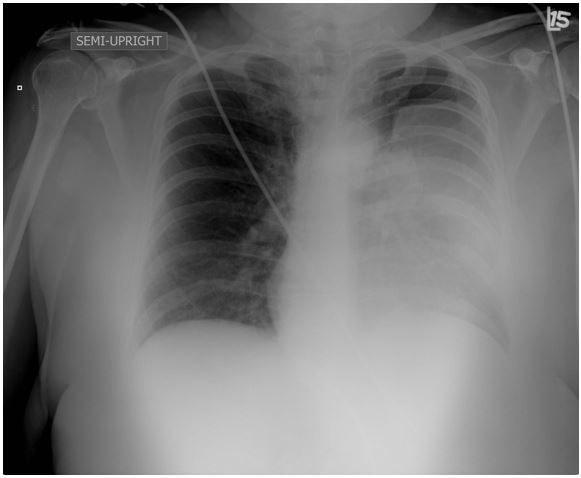

Chest x-ray

Based on the Chest x-ray above what would be the next best step in management of this patient?

- Admit the patient and start on antibiotics for community acquired pneumonia

- Perform an ultrasound guided thoracentesis

- Obtain a CT and plan for a bronchoscopy for tissue biopsy

- Inform the patient that his x-ray only shows an artifact (skin fold mimicking haziness) and discharge home.